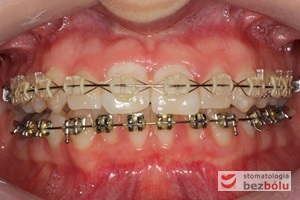

Pacjentka lat 22 zgłosiła się do naszej placówki celem podjęcia leczenia ortodontycznego. Głównym oczekiwaniem pacjentki była poprawa estetyki uśmiechu oraz brak ekstrakcji zębów na drodze do jej uzyskania. Ze względu na liczne stłoczenia zębów w górnym i dolnym łuku, dość duży materiał zębowy w porównaniu z bazą kostną, a także zgryz przewieszony boczny prawostronny po dokładnej analizie cefalometrycznej oraz analizie modeli diagnostycznych zastosowano leczenie bezekstrakcyjne z wykorzystaniem strippingu jako alternatywy dla usuwania zębów, mającego na celu uzyskanie miejsca w łuku na uszeregowanie zębów. Po fazie aktywnego leczenia trwającego 18 miesięcy zastosowano leczenie retencyjne w postaci szyny retencyjnej w łuku górnym oraz retainera stałego w łuku zębowym dolnym klejonego od kła do kła.